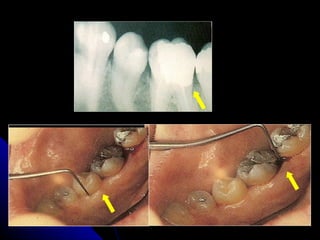

DIMENSÕES FISIÓLÓGICAS DO PERIODONTO DE PROTEÇÃO Para que promova um periodonto saudável,  -   a margem cervical deve estar  localizada nos limites compatíveis do controle de placa, - respeite  as dimensões fisiológicas do periodonto de proteção .

Espaço biológico:  é a distância  compreendida entre a base  do sulco histológico e a crista alveolar, constituído  pelo epitélio juncional e inserção conjuntiva.

A -  Para se  preservar a saúde periodontal   deve se  respeitar  o espaço biológico. B -  Para isso, o ideal é  que haja em torno de  3mm de estrutura dental sadia coronalmente  a crista alveolar  nos  preparos protéticos. A B

A  agressão  ao  epitélio juncional, e as fibras supracrestais , que constitui  barreira à infecção , provoca  inflamação gengival , que vai permanecer pós confecção da prótese, causando  danos irreversíveis  ao periodonto, com  formação de bolsa periodontal  e  migração do epitélio juncional

DIMENSÕES FISIÓLÓGICAS DOPERIODONTO DE PROTEÇÃO Para que promova um periodonto saudável, - a margem cervical deve estar localizada nos limites compatíveis do controle de placa, - respeite as dimensões fisiológicas do periodonto de proteção .